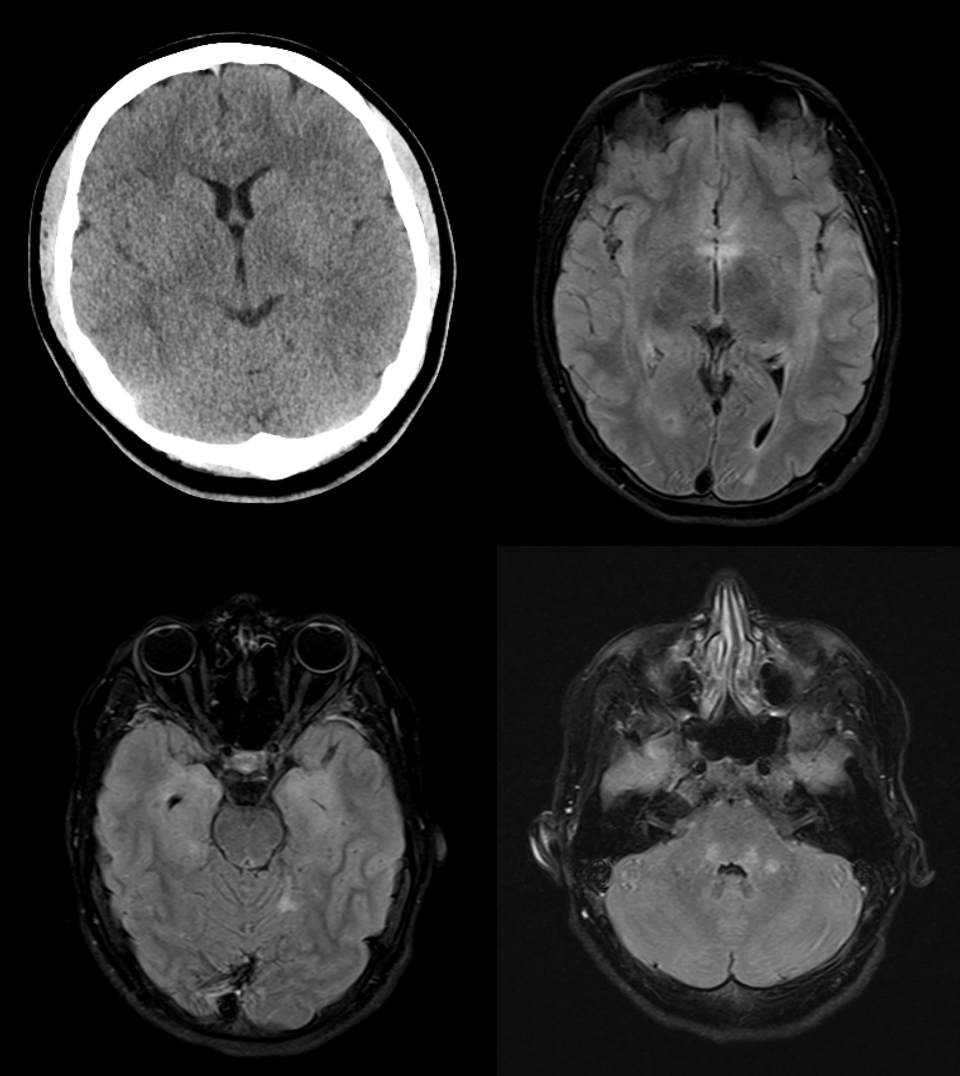

La TC eseguita in urgenza è stata utilizzata per escludere una patologia acuta come un'emorragia o un infarto. Successivamente è stata eseguita una risonanza magnetica (figura 1).

Figura 1

La risonanza magnetica ha mostrato una marcata iperintensità T2 nel midollo allungato, meno nel tegmento pontino, nel midollo cerebellare destro, nel midollo sottocorticale del corno posteriore sinistro, nel midollo insulare/temporale destro, intorno alle corna temporali, nel cingolo posteriore destro e frontalmente su entrambi i lati. I risultati dell’esame sono compatibili con un'encefalite limbica.